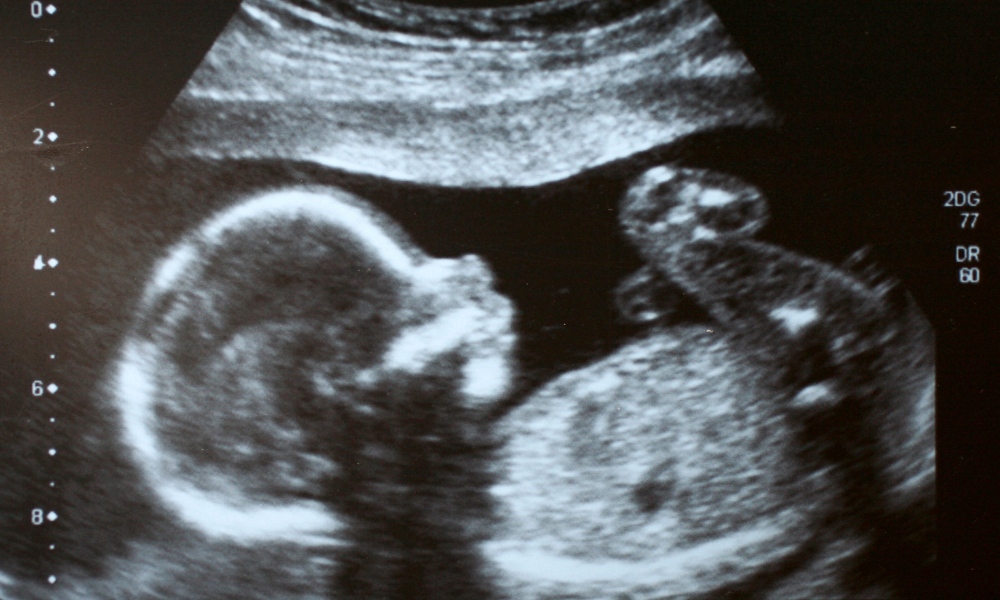

Bébé, macrosomie : est-ce vraiment inquiétant pour l'accouchement ?

Tu t’inquiètes de la macrosomie de ton bébé ? Comprends les enjeux de ce terme, les risques associés, et comment l'équipe médicale t'accompagnera pour un accouchement serein.

Bébé macrosome : un vrai défi pour l'accouchement ?

Le terme "bébé macrosomie" revient souvent en consultation, et c'est normal de se demander ce qu'il signifie pour toi et ton accouchement. Peut-être as-tu entendu ton médecin dire que ton bébé est "trop gros" pour un accouchement classique, ou peut-être as-tu simplement pris du poids, et cela t'inquiète. Pas de panique : parlons de ce que signifie réellement un bébé macrosomique et de ce que cela implique pour la suite.